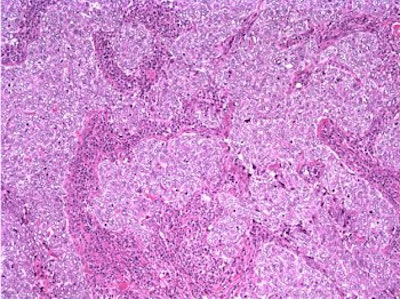

The patient underwent a lumpectomy with sentinel node biopsy. The pathology again showed extensive mitoses consistent with grade III invasive ductal carcinoma. Figure 4 (below) shows a representative microscopic section of the mass 4 cm from the nipple at a magnification factor of 100x. Figure 5 is the same area magnified 400x. Figure 6 shows a representative microscopic section from the other mass, which was 3 cm from the nipple magnified 100x. Figure 7 is magnified 400x. The tumors were estrogen receptor- and progesterone receptor-negative. Two sentinel nodes were negative.

Figure 6: Above, IDC right breast, 10 o'clock, 3 cm from the nipple magnified 100x. Figure 7: Below, IDC right breast, 10 o'clock, 3 cm from the nipple magnified 400x. |